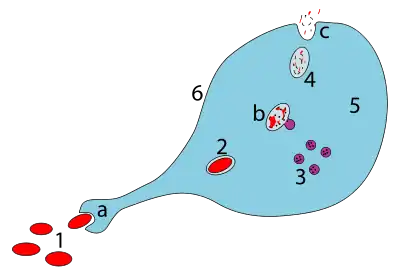

a. Ingestion through phagocytosis, a phagosome is formed

b. The fusion of lysosomes with the phagosome creates a phagolysosome; the pathogen is broken down by enzymes

c. Waste material is expelled or assimilated (the latter not pictured)

Parts:

1. Pathogens

2. Phagosome

3. Lysosomes

4. Waste material

5. Cytoplasm

6. Cell membrane